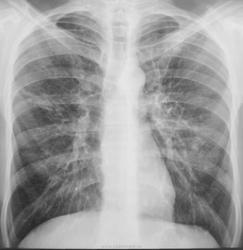

Пациента довольно успешно лечили по поводу "пневмонии", да и субъективно пациент отмечал улучшение, НО перед выпиской, ВДРУГ, при микроскопии были обнаружены МБТ.

Динамика в процессе лечения.

Двусторонняя пневмония в таких-то сегментах (чего-то не увеличиваются...). Остальное - в динамике.

Д/д ряд: пневмония, саркоидоз и м.б. туберкулез.